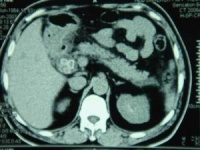

4.CT断层扫描CT对胆总管结石的诊断优于B超,准确率可达80%左右。但难以显示胆管系统病理改变和结石数量、大小、分布等状况。